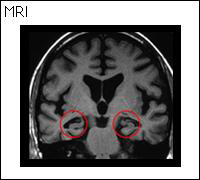

正常 アルツハイマー型認知症

アルツハイマー型認知症:全体的に脳が痩せて特に短期的記憶をつかさどる海馬が小さくなっている

睡眠時無呼吸を放置すると、認知症の発症を促進する。睡眠時無呼吸をCPAPにより治療することは認知症予防に効果がある。